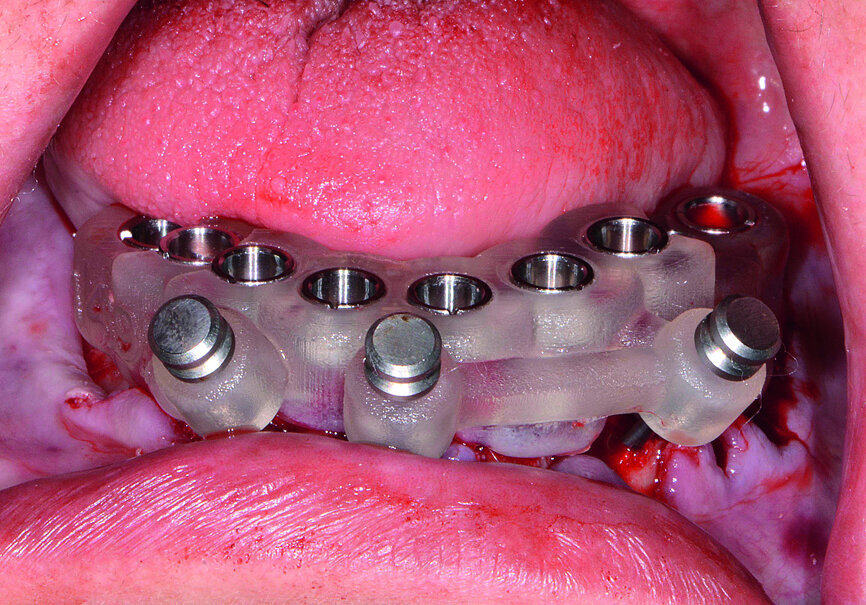

Fig. 15: Implants and healing caps with surrounding grafting.

Next, the patient’s untreatable mandibular teeth (Fig. 13) were extracted using the Physics Forceps (GoldenDent), a flap was reflected, and an alveoloplasty was performed. A bone-supported guide was seated in order to control the location and angulation of the implant osteotomies (Fig. 14). As the Hahn Tapered Implants were threaded into place, their deep, sharp threads engaged the walls of the socket sites and helped maintain proper position toward the lingual aspect. Because of anticipated tissue swelling as a result of the bone levelling procedure, 5 mm high healing abutments were connected to the implants in the lower arch (Fig. 15). The immediate dentures were soft-relined with Mucopren (Kettenbach) to seat over the Hahn Tapered Implant Healing Abutments, the hourglass shape and undercuts of which provided a degree of retention that enhanced dental function for the patient during healing (Fig. 16).